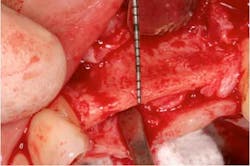

Fig. 2